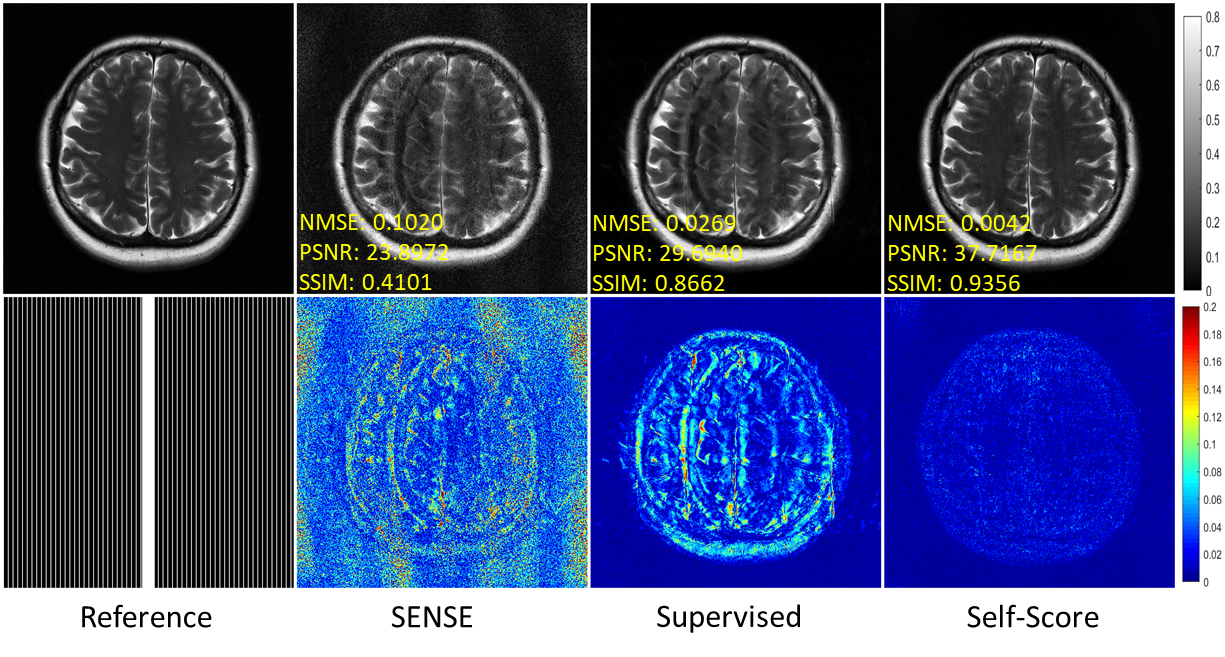

5.2.2 Data Shift

In this section, we verified the performance of various methods when the data type (anatomies) were inconsistent during training and testing. Figure 6 shows the results of various methods trained on fastMRI knee data and reconstructed on fastMRI brain. The self-supervised method based on k𝑘k-space interpolation in the paper is no longer applicable due to the different number of channels in the two data sets. Similar to the pattern shift experiment results, SENSE performs poorly, although it is not affected by data shift. The supervised learning method reconstructs the image aliasing pattern residuals, verifying that it also generalizes poorly in data shift. The proposed method in this paper can accurately reconstruct images, thus verifying its superior generalization in data shift.

Refer to caption

Figure 6: Reconstruction results of fastMRI brain data under uniform undersampling at R=6𝑅6R=6. The corresponding models were trained on fastMRI knee data. The values in the corner are NMSE/PSNR/SSIM values of each slice. Second and third rows illustrate the enlarged and error views, respectively. The grayscale of the reconstructed images and the color bar of the error images are at the right of the figure.

Table 3: Quantitative comparison for various methods on the fastMRI brain dataset.

Datasets Quantitative Evaluation

& Methods NMSE PSNR(dB) SSIM

fastMRI Brain SENSE 0.1703±plus-or-minus\pm0.1559 22.05±plus-or-minus\pm1.56 0.31±plus-or-minus\pm0.09

Supervised 0.0273±plus-or-minus\pm0.0124 29.37±plus-or-minus\pm1.22 0.85±plus-or-minus\pm0.03

Self-Score 0.0068±plus-or-minus\pm0.0042 35.53±plus-or-minus\pm1.31 0.90±plus-or-minus\pm0.03

The above experiments verified that the proposed method can accurately reconstruct images and has good generalization ability without the fully sampled training data.